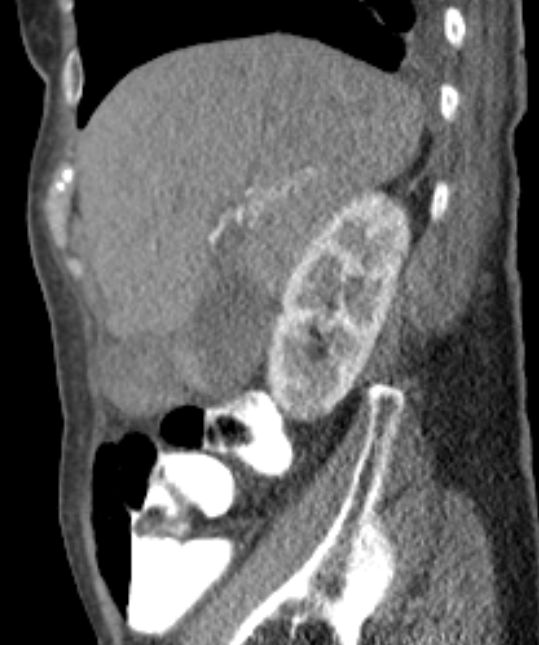

Lebermetastase |

86-jähriger Mann, bei dem vor 9 Monaten eine Cholezystektomie wegen gedeckt perforierter Cholezystitis vorgenommen wurde. Jetzt Verdacht auf Leberabszess. Die laparoskopische Biopsie ergab ein Adenokarzinom. Die Nachbefundung der Gallenblase erbrachte immunhistochemisch den Nachweis eines Gallenblasenkarzinoms. | ||